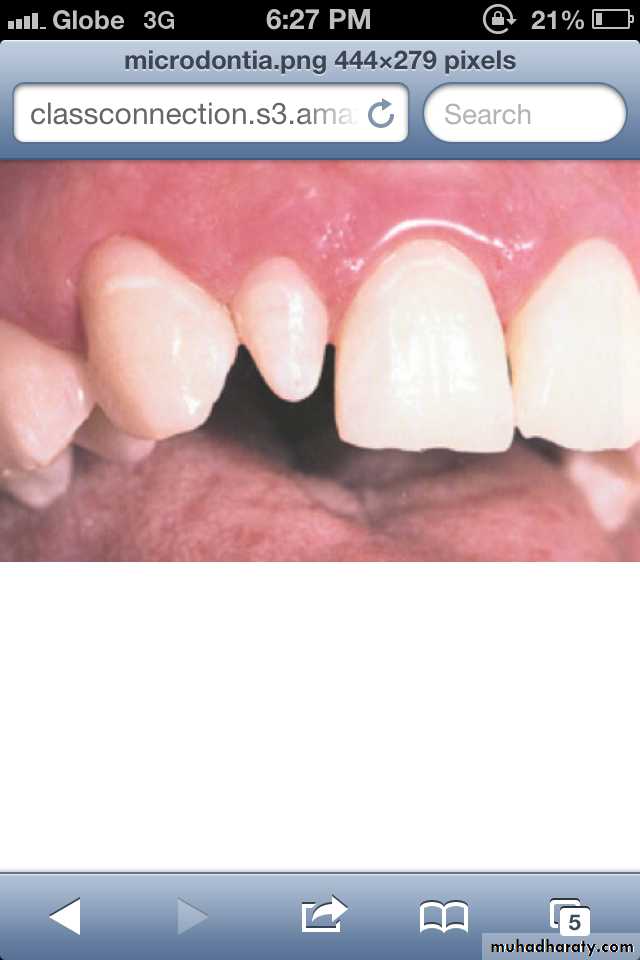

(3) Focal/Localized MicrodontiaCommon condition.

Affects most often maxillary

lateral incisior + 3rd molar.

These 2 teeth are most often

congenitally missing.

sides converge or taper

together incisallyforms cone-shaped crown

root is frequently shorter

than usual.

(3) Focal/Localized Microdontia